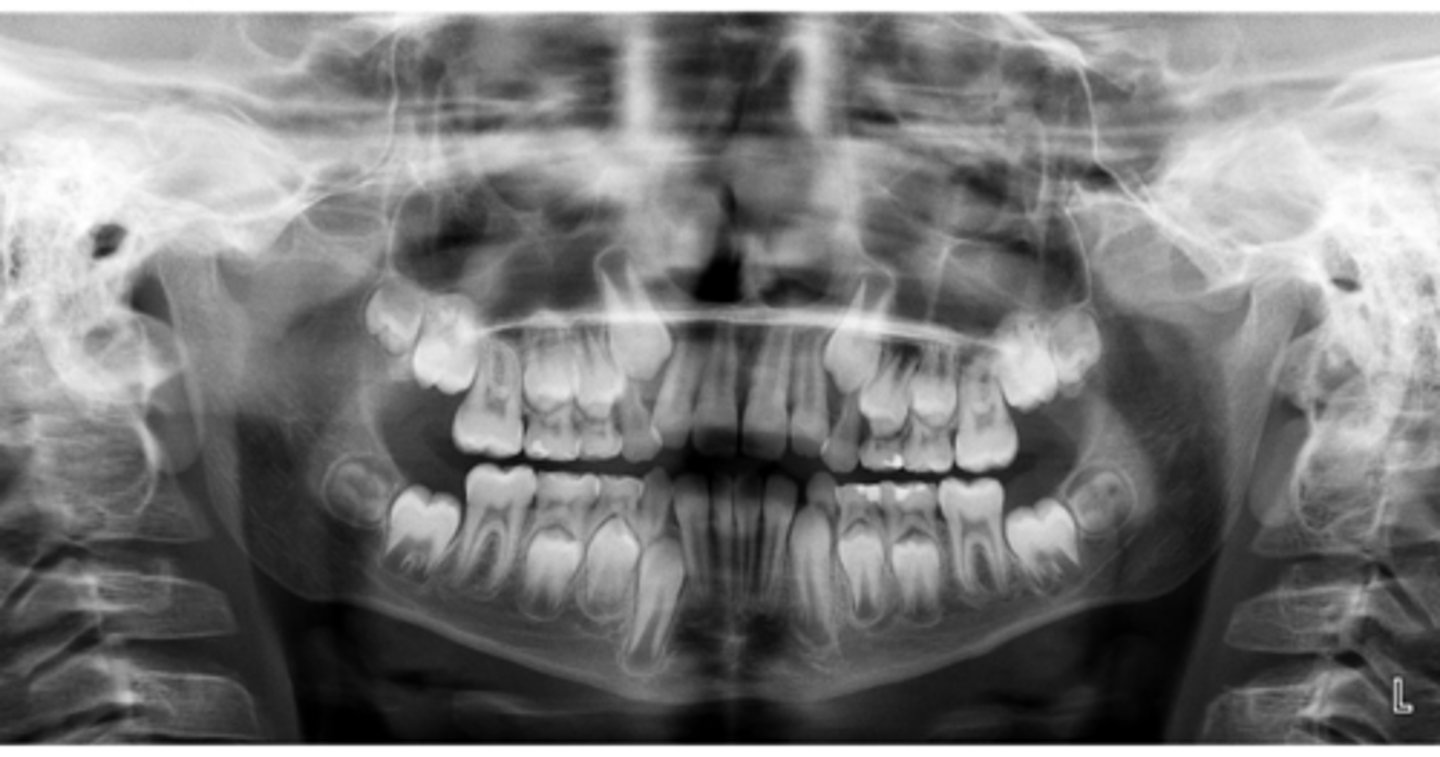

Premolar #13 (unerupted in pano) is more tilted than the opposing side (#4), which indicates an ectopic eruption pattern.

(Primary teeth w/o resorbing roots is also present)

What abnormalities/concerns do you see in this pano?

Third molars and mandibular right second premolar

Are there any congenitally missing teeth in the maxillary arch?

#29 (mandibular right second premolar)

Are there any congenitally missing teeth in the mandibular arch?

mandibular right second molar

Are there any retained primary teeth?

maxillary canines

Are there any impacted teeth?

Yes

Is there crowding?

More or less

Are the condyles symmetrical?

Maybe?

Is there any pathology?

Are there any ankylosed primary teeth?

No, just one in an odd position

Is there any ectopic eruption?

No

Are there supernumerary teeth?